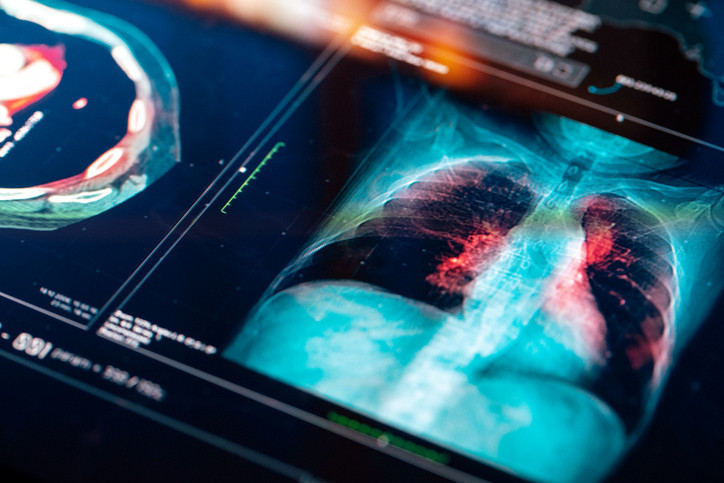

‘Yürüyen zatürre’ ve gençlerdeki risk

Bağışıklık uzmanı Dr. Samira Jeimy, son dönemde özellikle gençlerde ‘yürüyen zatürre’ (mycoplasma pneumoniae) vakalarında devasa bir artış gördüğünü belirtiyor.

Yürüyen zatürre, hafif bir akciğer enfeksiyonudur. Belirtileri arasında boğaz ağrısı, hapşırma, öksürük, baş ağrısı, hafif titreme ve düşük dereceli ateş bulunuyor.